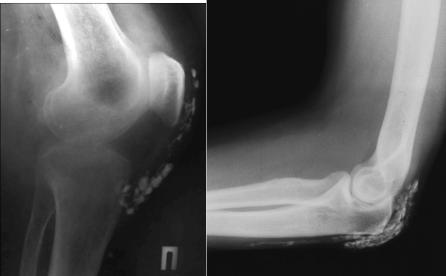

Кальцинаты— небольших размеров подкожные отложения солей кальция, обычно появляются на пальцах кистей и на участках, часто подвергающихся травмам. Кальцинаты могут вскрываться с выделением творожистой массы (рис.5-3).

Рис. 5-3. Кальциноз мягких тканей.